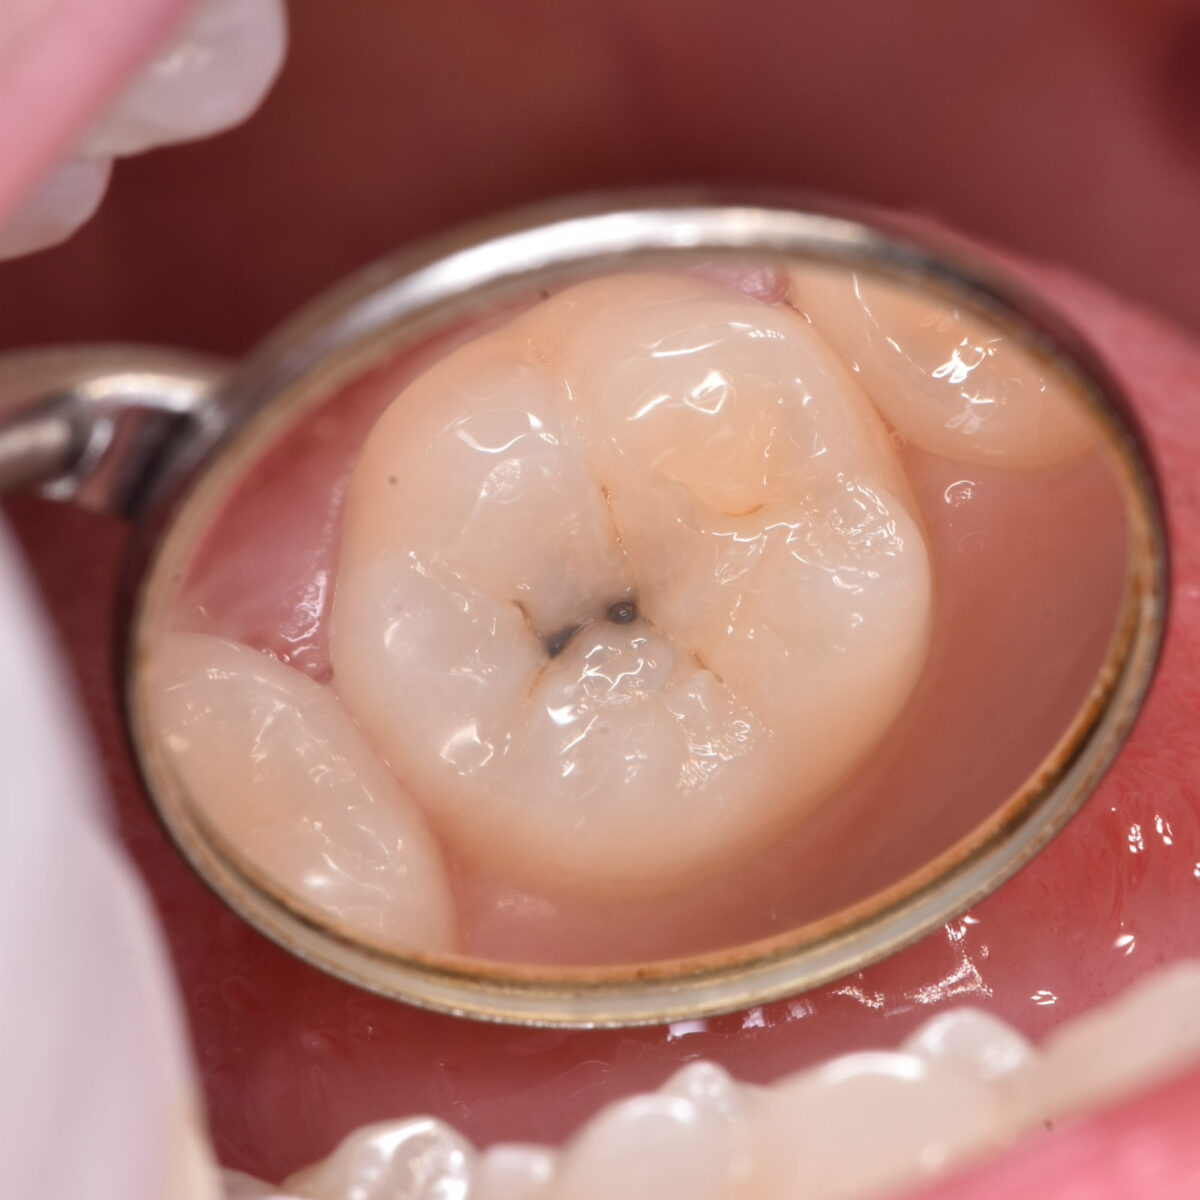

外側から一目でむし歯の大きさがわかるわけではないことを教えてくれるケース

歯の状態を見て、むし歯の大きさはわかるのか? 【東京メトロ東西線妙典駅 徒歩5分の歯医者】市川、妙典の歯科医院、めぐりデンタルクリニックの梶原です。 むし歯の状態は目で見てわかるの…